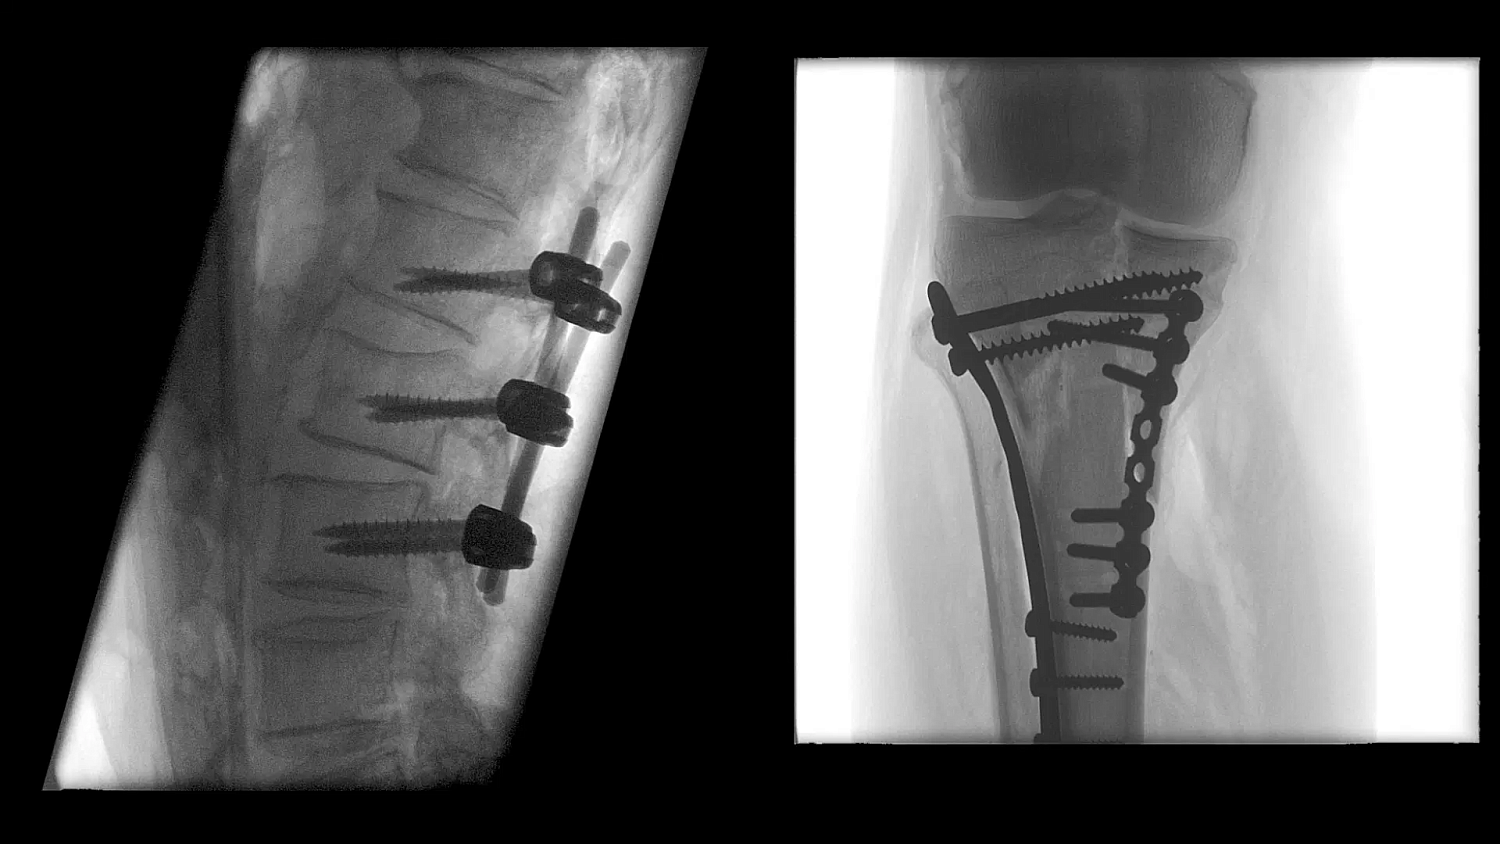

- Улучшенная цепочка визуализации матричного детектора с технологией CMOS: интеллектуальные алгоритмы автоматически регулируют яркость и контрастность, обнаруживают движение, улучшают края и оптимизируют визуализацию металла для улучшения изображения окружающих тканей

- SpotAdapt и сенсорные жесты: SpotAdapt автоматически оптимизирует параметры визуализации в соответствии с интересующей анатомией. Сенсорные жесты, как на планшете, позволяют коллимировать, поворачивать и переворачивать изображения, а также использовать преимущества SpotAdapt всего одним пальцем.

Больницы сталкиваются с ростом стоимости медицинского оборудования, поэтому им необходимо оправдать инвестиции. Cios Flow — это многофункциональная система, которую можно использовать в различных областях — ортопедической и травматологической хирургии, хирургии позвоночника, сосудистой хирургии и т. д. — позволяя повысить эффективность использования своих ресурсов.